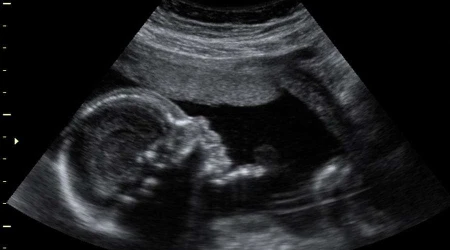

Los ultrasonidos en casos de embarazos son usualmente momentos íntimos, realizados en una oficina privada de un médico. Sin embargo, algunas voluntarias embarazadas y un grupo provida de Nebraska han realizado ultrasonidos en las escuelas para que los estudiantes puedan presenciar en vivo el milagro de la vida.

Desde el 2016, los voluntarios de la organización han presentado imágenes de ultrasonido de una gestante de 10 a 30 semanas en colegios públicos y privados de Omaha (Nebraska, Estados Unidos). Además del ultrasonido, se da información sobre la adopción por parte de una persona con experiencia en el tema.

Luego, dos técnicos se ofrecieron como voluntarios para operar la unidad de ultrasonido durante las presentaciones. Schaefer declaró que muchas mujeres embarazadas también se ofrecen como voluntarias para mostrar a sus bebés en las ecografías.